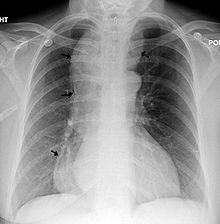

من الأعراض الأخرى الأقل شيوعا قلس الطعام غير المهضوم ونقص الوزن وحرقة الفؤاد والألم الصدري. قد يؤدي قلس المواد الطعامية إلى السبيل التنفسي أثناء الاستلقاء ليلا إلى حدوث الاختناق أو ذات الرئة الشفطية (ذات الرئة بالارتشاف). غالبا ما يكون نقص الوزن خفيفا ما بين 5 إلى 10 كغ. يمكن أن يكون سبب حس حرقة الفؤاد لدى بعض المرضى هو وجود داء الجزر المعدي المريئي مستبطنا لديهم، وقد يكون بسبب التخريش المباشر للمواد الطعامية ومستقلباتها المحصورة في المريء. قد يكون الألم الصدري هو العرض الذي يراجع به بعض المرضى بشكل مشابه للألم القلبي. يذكر أيضا أن بعض المرضى الذين يراجعون الطبيب بما يعرف باللقمة الهستيرية يعانون من من تعذر الارتخاء المريئي.[2][4][5]